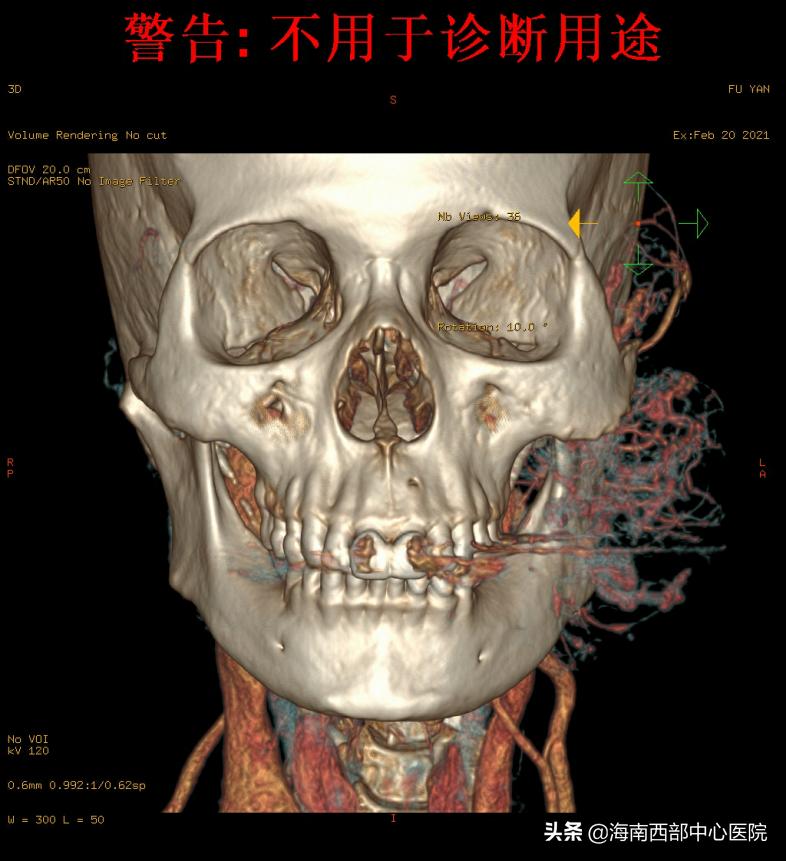

患者的信任,让西部中心医院的团队有了很大的信心,但患者复杂的病情不得不让参与手术的每一个医务人员变得谨慎细微。患者准确的诊断应该是间质为主的动静脉畸形,范围从颞部、颅底区域,到达咽旁、颌下区域,最大的风险就是周围血管全部扩张、增粗,术中在切除的时候会遇到非常多的像拇指一样的血管,稍有不慎,就会形成“喷射性”的快速失血,可以直接打到手术室天花板上,每次出血量都在200-300毫升,约占到人体总血量10%。而人体快速失血超过30%,就会引起严重的心脑血管问题,严重的可以导致死亡。尤其是头颈部,重要结构众多,到了动静脉畸形的深部,由于与周围的颅底区域的血管、神经和肌肉没有明确的界限,难以进行剥离,不可避免的会造成大量快速的出血。同时,这种疾病治疗的难点,就是在这个阶段,周围组织不停的出血,周围又有面神经、下颌骨等众多功能器官和颈动脉、颅底等重要结构,让外科医生不敢下手,但快速的失血又不给外科医生过多的迟疑机会。对于口腔颌面外科医生来说,动静脉畸形是最考验外科医生功力的疾病之一,对麻醉团队来说,由于快速的失血,血压的维持和多脏器循环的维护也是巨大的考验,是对医院外科实力的综合考验。

鉴于患者的病情,张院士在第一次面诊的时候就提出了“栓塞+切除”的综合治疗方案,这个治疗方法也是他的“独门绝活”之一,具有着丰富的治疗经验,通过颅面部软组织动静脉畸形的介入栓塞可栓塞缩小病灶,以利于手术切除。可降低病变的流速,控制并发症的发生以及作为手术前的辅助性栓塞。他的学生,现挂职于海南西部中心医院的杨溪副院长,按照多年来形成的治疗默契,有条不紊地组织着术前的准备工作,完善各类影像学检查。因患者病情复杂,手术难度大,在海南省属首例,该院张少明院长召集相关科室会诊,讨论术前备血、麻醉、术中栓塞及切除的细节,术后管理,甚至手术器械,都进行了一一的清点及准备。